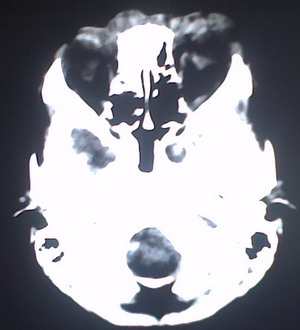

以下是引用jiajie在2009-2-3 20:02:00的发言:[br]脑室周围白质区可见大量斑片状钙化,部分融合成带状,双侧侧脑室及第三脑室扩大。[br]考虑弓形体原虫感染。(先天性宫内感染、torch综合症)

以下是引用lkc8963在2009-2-3 21:15:00的发言:[br]临床眼睑可见静脉扩张,ct双侧眼上静脉亦示扩张,颅内钙化以皮层\\软脑膜为主而不是位于白质和室管膜,再加上静脉窦异常,还是应该考虑静脉血管瘤病,可能为较复杂的血管畸形.

以下是引用卜一在2009-2-4 9:21:00的发言:[br]sturge-weber综合征:面部三叉神经分布区的毛细血管性或海绵状血管瘤以及同侧枕、顶或额叶软脑膜的血管瘤(以静脉性为主)。脑皮质,特别是第二三层,毛细血管可有增厚和钙化。局部发生层状坏死、神经细胞脱失、萎缩、胶质细胞增生及钙盐沉着。可根据面部典型分布的特征性皮痣作出诊断。头颅ct:发现面部血管瘤同侧的脑内病理钙化影,呈双层线条波浪形、脑回形或树枝形。本例支持:sturge-weber综合征![br]